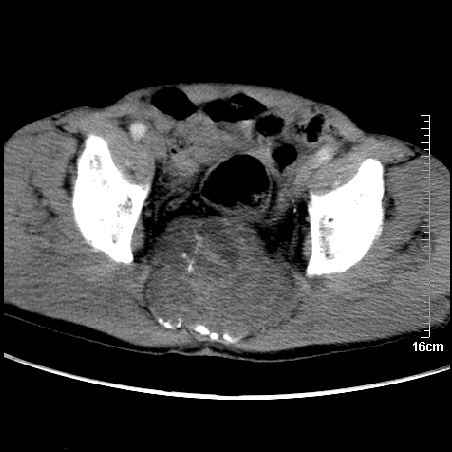

标题: CT16886:骶尾部占位:1.脊索瘤?2.巨细胞瘤? [打印本页]

标题: CT16886:骶尾部占位:1.脊索瘤?2.巨细胞瘤?

增强:

1、骶尾部巨大软组织肿块,部分骶尾骨以被软组织肿块代替,呈不规则侵蚀;病变突向盆腔内;增强扫描病变呈不均质强化;首先考虑脊索瘤。不支持的一点就是病变内无钙化。

2、发生于骶尾椎者须与骨巨细胞瘤鉴别,骨巨细胞瘤一般发在上疗骶椎,肿瘤内无钙化,一般无侵袭性生长的表现。